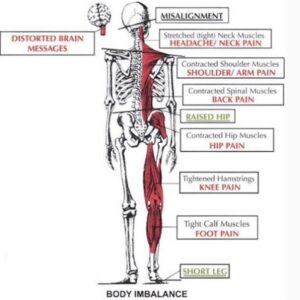

Disordini posturali

L’equilibrio del sistema occipito-atlanto-assiale risulta fondamentale per avere una postura che si rivolge correttamente sugli assi di tutto il corpo. La posizione e il peso della testa se ben allineato da questo sistema permette di avere una maggior equilibrio per tutti gli assi vertebrali della colonna. Inoltre c’è una forte correlazione con la mandibola, infatti un mal posizionamento mandibolare modifica la posizione della testa e il sistema occipito-atlanto-assiale deve attuare tutti i compensi necessari per ritrovare un equilibrio posturale, generando però una serie di compensi su tutta la colonna e su tutto il corpo. Anche i piedi rappresentano un ingresso sensoriale posturale importante che può riflettersi su tutte le articolazioni del corpo fino ad arrivare al sistema occipito-altanto-assiale.